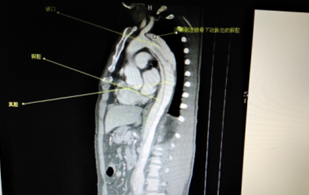

術(shù)前CT檢查(顯示為主動脈夾層)

據(jù)我院外二科主治醫(yī)師魏宇介紹,“夾層”就是兩層之間插進去的一層,比如把一片面包從中劈開,塞進去一些培根生菜就是“夾層”了。而主動脈是人體內(nèi)最大的動脈,心臟射出的血流首先都進入主動脈,再分流到各個分支動脈。主動脈夾層就是指主動脈腔內(nèi)的血液從主動脈內(nèi)膜撕裂口進入主動脈壁內(nèi),使主動脈壁中層形成夾層血腫,并沿主動脈縱軸擴展的一種心血管系統(tǒng)的疾病。因為主動脈是身體的主干血管,承受直接來自心臟跳動的壓力,血流量巨大,出現(xiàn)內(nèi)膜層撕裂,如果不進行恰當(dāng)和及時的治療,破裂的機會非常大,死亡率也非常高。